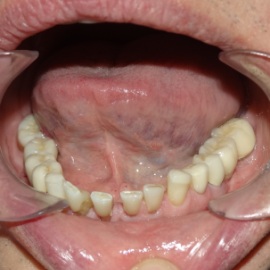

Brakujących pięć zębów dolnych w odcinku wargowym. Rekonstrukcja tkanek i rehabilitacja protetyczna.